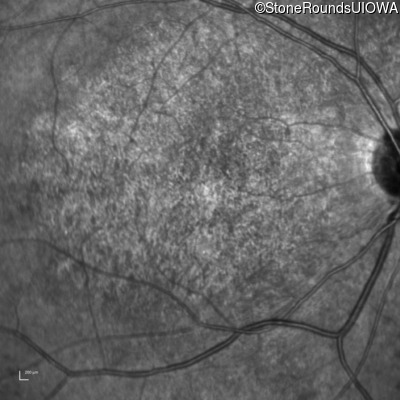

Infrared Fundus Photograph - Left - 10/125 -2 sc

Exemplar